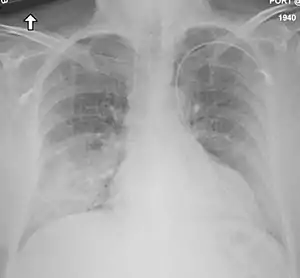

Síndrome respiratória do Médio Oriente (SRME ou MERS) é uma infeção respiratória viral causada pelo coronavírus MERS (MERS-CoV).[1] Os sintomas podem variar de ligeiros a graves.[4] Os mais comuns são febre, tosse, diarreia e falta de ar.[1] Os sintomas geralmente começam-se a manifestar de 2 a 14 dias após a exposição ao vírus.[2] A doença é geralmente mais grave em pessoas com outros problemas de saúde.[4]